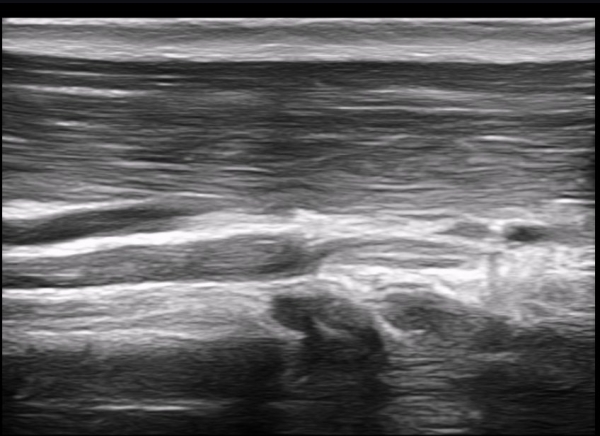

±ÙÀ°ÇǺνŰæÀÇ Á¾´Ü¸é°Ë»ç¿¡¼­ ±ÙÀ°ÇǺνŰæÀÇ ±¹¼ÒÀû ÇùÂø°ú ±ÙÀ§ºÎÀÇ Àú¿¡ÄÚ ºÎÁ¾ÀÌ °üÂûµÈ´Ù

(»çÁø 4, 5, 6,7) À̰ÍÀº ½Å°æÀÇ ¿°Àü(torsion)¿¡ ºÎÇÕÇÏ´Â ¼Ò°ßÀÌ´Ù.